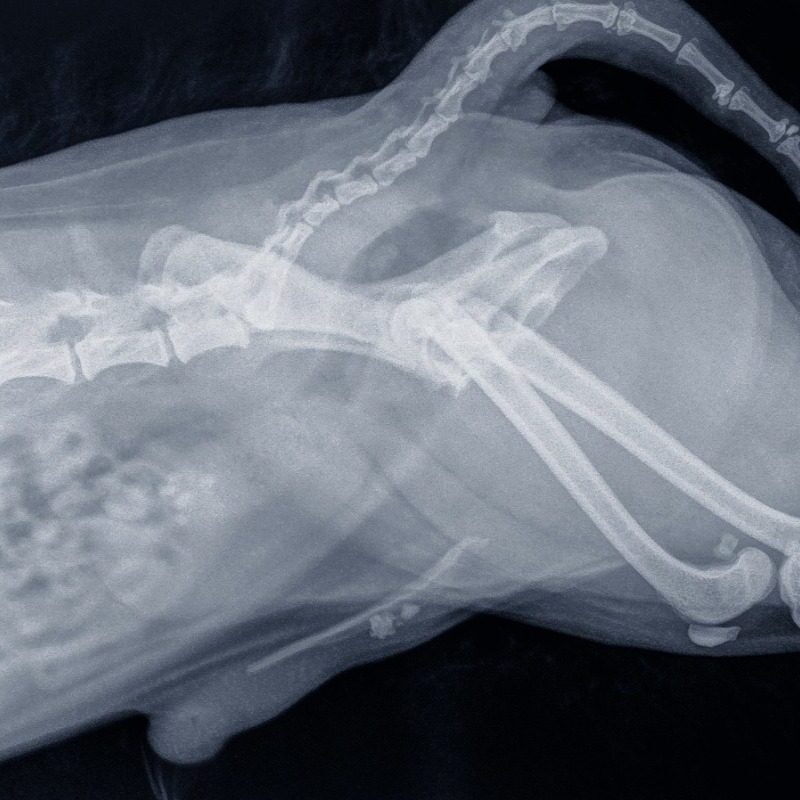

Perineal Urethrostomy x-ray of a cat

Male cats have a very long, narrow urethra that narrows even further at the tip of the penis, making them prone to blockages from stones, crystals, or inflammation. A PU surgery removes the penis and the narrow part of the urethra, creating a new, wider opening closer to the bladder.